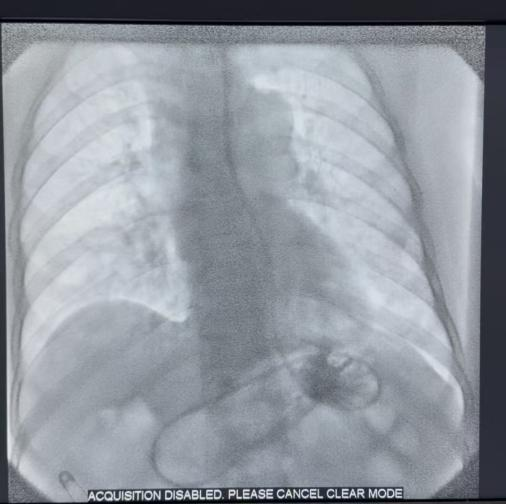

营养是患者耐受后续治疗的基础,赵延军副主任决定在DSA引导下实施空肠营养管置入术。在师佩护士长及郭倩医师的密切配合下,赵延军副主任凭借娴熟的技术,精准定位、小心操作,成功将营养管精准置入预定位置,一举解决了患者“吃饭难”的核心问题,为后续治疗筑牢根基。

解决营养支持后,团队立即启动气道疏通计划。气管镜下显示气管下段新生物阻塞已达90%,巨大的气管食管瘘口清晰可见。顾兴主任与赵延军副主任协同操作,采用硬镜与软镜双镜联合的方式,在内镜护理团队高效配合下,成功为患者置入气管支架。支架张开后,原本近乎闭塞的气道瞬间变得通畅,同时完美覆盖了瘘口,一举解决了呼吸梗阻和瘘口返流两大难题。

术后,患者呼吸困难症状立刻显著缓解,生命体征趋于平稳,并通过空肠营养管获得了宝贵的营养支持。家属紧锁的眉头终于舒展, 向医护团队表达由衷的感激之情。